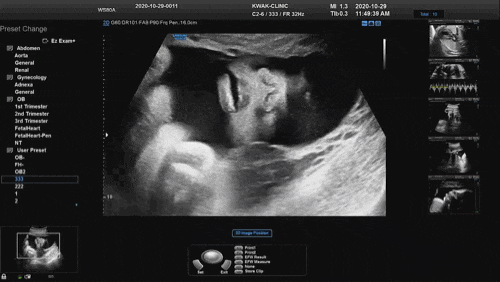

임신 36주차/성남 곽여성병원/태동검사/이제산후조리원 산전마사지/이케아 기저귀교환대&트롤리

임신 36주차 10개월 진입!! 초음파 BPD = 8.71cm (35주1일) HC = 31.05cm (35주1일) AC...

임신 37주차/성남 곽여성병원/내진&GBS균 검사/이제산후조리원 산전마사지/결혼기념일

임신 37주차! 36주 부터 매주 산부인과에 가야한다 이번에는 오랜만에 오빠와 함께 간 산부인과 초음파 B...